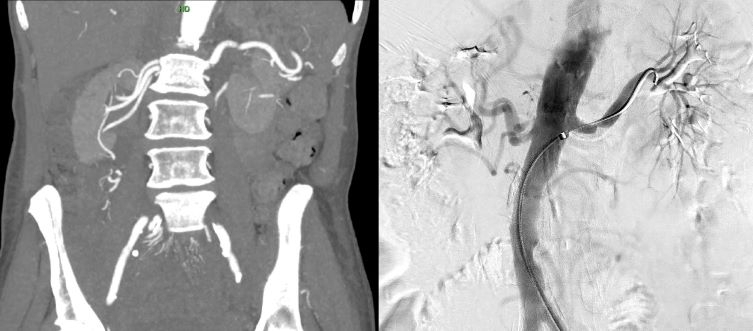

Initial evaluation, including laboratory tests and RA ultrasound, showed no abnormalities. However, a CTA of the abdomen revealed a single heavily calcified L main RA with severe atherosclerosis extending into the lumen of the aorta and the proximal L main RA. Three RAs supply R kidney with questionable stenosis of superior, smaller R RA. Atherosclerotic plaque is present at the origin of the inferior R RA, but no definitive significant stenosis is detected.

Unilateral RAS and multiple ARAs were suspected to cause HTN and FPE. An aortogram with possible RA stenting was recommended by vascular surgery. It confirmed > 75% stenosis in the L RA, prompting stent deployment. However, no significant stenosis was observed in R ARAs.